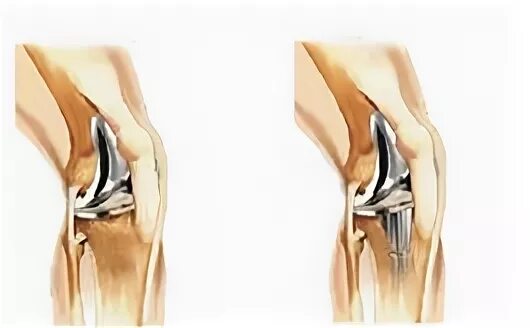

В каком случае меняют сустав